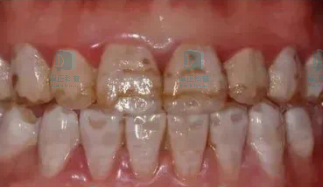

牙齿本身颜色异常

常见的有牙釉质发育异常、牙本质发育异常、氟斑牙等。

1

牙釉质发育不全;

图片

牙釉质发育不全的病因尚不明确,目前认为是一种多因素疾病,包括全身系统疾病、环境因素、表观遗传因素等引起的牙釉质矿化缺陷,牙釉质发育不全的孩子要做好防龋工作,对缺损较严重的牙釉质进行冠修复,成年后再根据情况进行牙齿修复